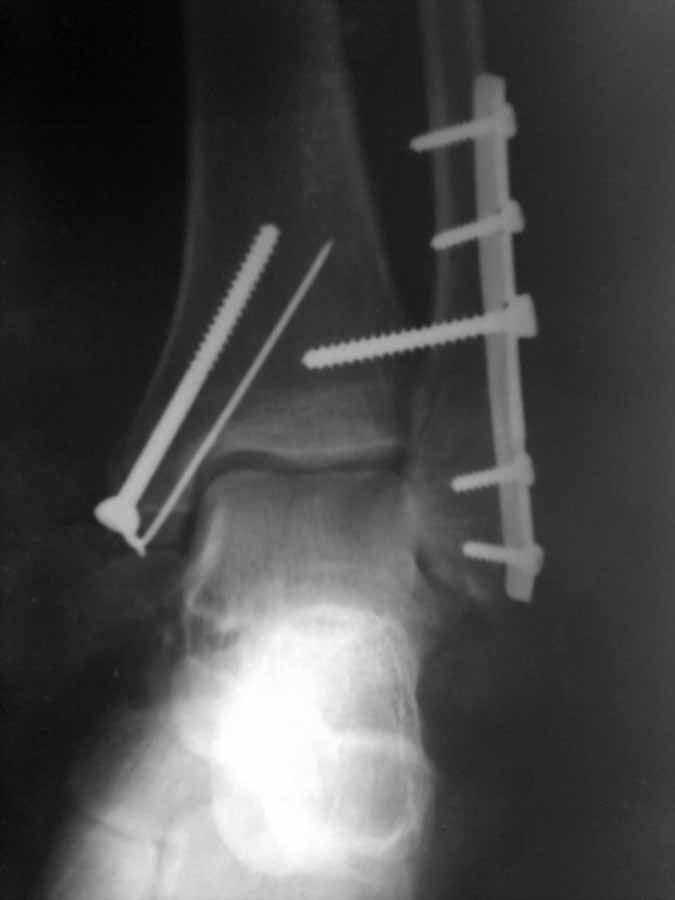

После операции высказали ряд замечаний. Не то что бы имею грандиозный опыт, но результат считаю достаточно удовлетворительным по крайней мере для того, что бы делать реМОС (так решило начальство.

Внутренняя лодыжка недорепонирована. Кортикальный винт в ней... а спонгиозника не было?

Нижние винты в треть трубчатой пластине чуть бы подлиннее и позиционный винт то же.

Наружная лодыжка репонирована хорошо, подвывиха нет.

Тем не менее, смущает отсутствие стягивающего винта, который должен был быть проведен перпендикулярно плоскости перелома наружной лодыжки в передне-заднем (или обратном) направлении. Тогда 1/3- трубки работает как нейтрализующая пластина. Без стягивающего винта она никакая - ни компрессирующая , ни нейтрализующая. Она просто слабая. Второе, мы ни чего не знаем о межберцовом винте. Нужен ли он был вообще? На каком этапе он был введен? Как подготавливались отверстия перед его введением? При пристальном рассмотрении имеющегося снимка создается впечатление, что этот винт работает как стягивающий, а не как позиционный, удерживающий, и имеется избыточное сдавление синдесмоза и из-за этого смещение тарана кнутри на 1-1,5 мм, что не позволило идеально отрепонировать медиальную лодыжку.. Хотя с последней проблем меньше всего.

Операция осуществлялась через 2 часа после травмы. начиная с латеральной лодыжки при достижении репозиции 2-х больших отломков и кусочка с прикрепленным синдесмозом произведен МОС пластиной с прижиманием кусочка под пластиной. МОС медиальной лодыжки, позиционный винт (сильно не стягивал, закручено при сгибании голеностопа 90 градусов до ощущения малейшего сопротивления). Винт в медиальной лодыжке - маллеолярный, а не спонгиозный, по моему последний тут менее нужный.

Больному 29 лет. Операция осуществлялась через 2 часа после травмы. начиная с латеральной лодыжки при достижении репозиции 2-х больших отломков и кусочка с прикрепленным синдесмозом произведен МОС пластиной с прижиманием кусочка под пластиной. МОС медиальной лодыжки, позиционный винт (сильно не стягивал, закручено при сгибании голеностопа 90 градусов до ощущения малейшего сопротивления). Винт в медиальной лодыжке - маллеолярный, а не спонгиозный, по моему последний тут менее нужный.

Похоже, что у вашего пациента повреждение голеностопа типа Б т.е.линия перелома наружной лодыжки проходит на уровне синдесмоза: репозиция перелома и его фиксация( компрессионный винт или антиглайдин пластина) - вполне достаточно для стабилизации перелома и нет необходимости в проведении винта для фиксации дистального межберцового синдесмоза.